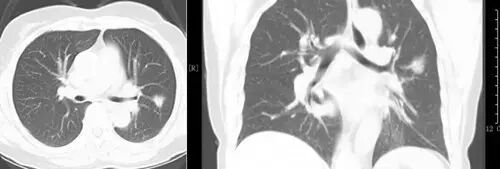

過(guò)去,常見(jiàn)的肺癌檢查工具是只有胸部X光檢查,但它很難看出1cm以下的結(jié)節(jié)。隨著肺癌診斷技術(shù)的發(fā)展,低劑量螺旋CT(LDCT)掃描目前已經(jīng)成為早期肺癌篩查的最佳方法。并得到全球醫(yī)師的認(rèn)可和遵循,美國(guó)于2011年和2015年兩次將其列入肺癌NCCN指南中。 我國(guó)在2015年也把LDCT列入早期肺癌篩查,并做了規(guī)范與共識(shí),同年5月在中華放射學(xué)雜志第49卷第5期發(fā)表了該規(guī)范與共識(shí)。

美國(guó)曾有一項(xiàng)針對(duì)50至74歲有抽煙病史民眾的大規(guī)模肺癌篩檢。研究顯示,低劑量螺旋CT有助于發(fā)現(xiàn)早期肺癌,特別是周?chē)头切〖?xì)胞肺癌,其檢出率約為胸部X光的10倍。

并且,相較于胸部X光檢查,低劑量CT掃描可降低20%肺癌死亡率。研究證實(shí)了低劑量CT的年度篩查可發(fā)現(xiàn)85%的Ⅰ期肺癌,其后手術(shù)切除的10年生存率達(dá)92%。